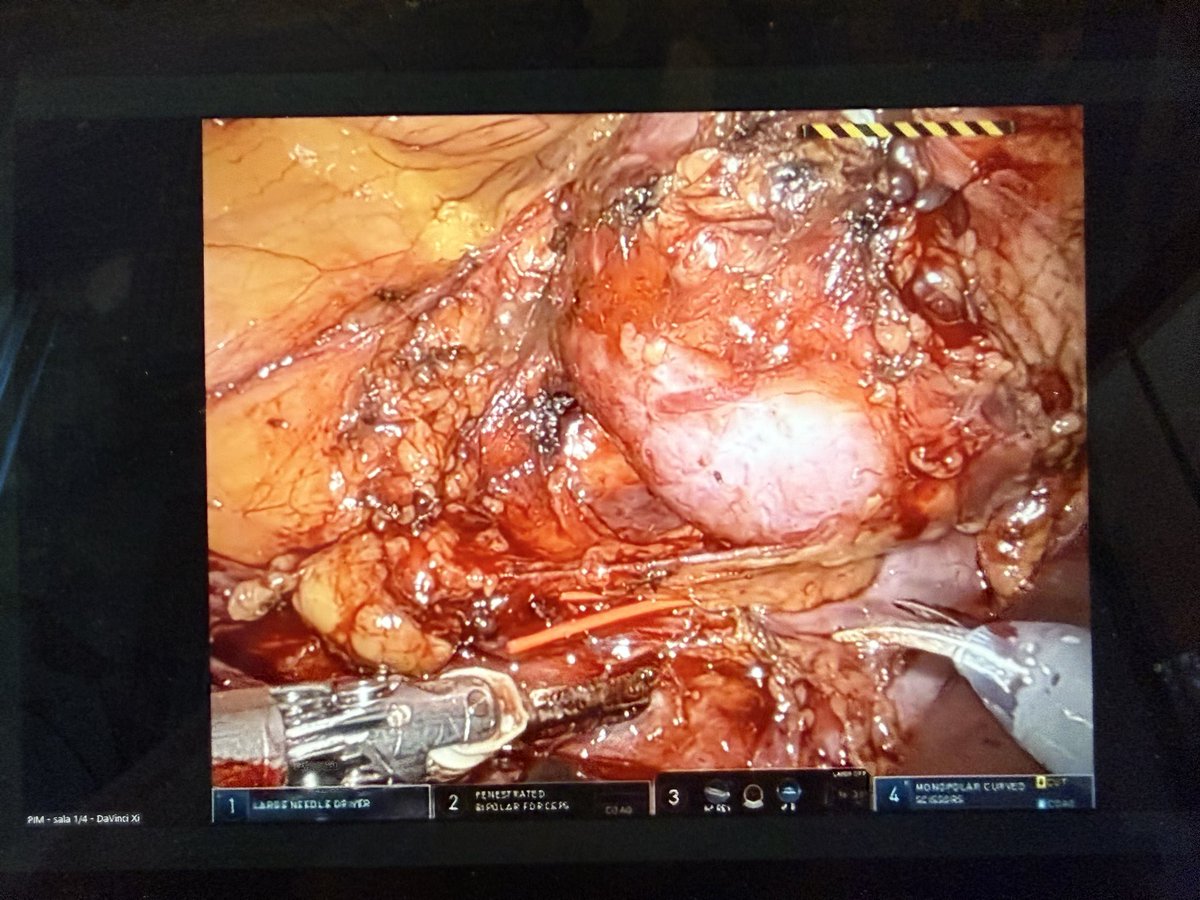

Following the Central European Robotic Event from home thanks to @surgquest @pawelwisz @Ruben_De_Groote performing a difficult partial nephrectomy of a hilar tumor! Also tune in to see @PuliattiStefano @alexmottrie @paolo_delloglio @gdnaeyer @SimoneCrivella2 @BPeyronnet &…